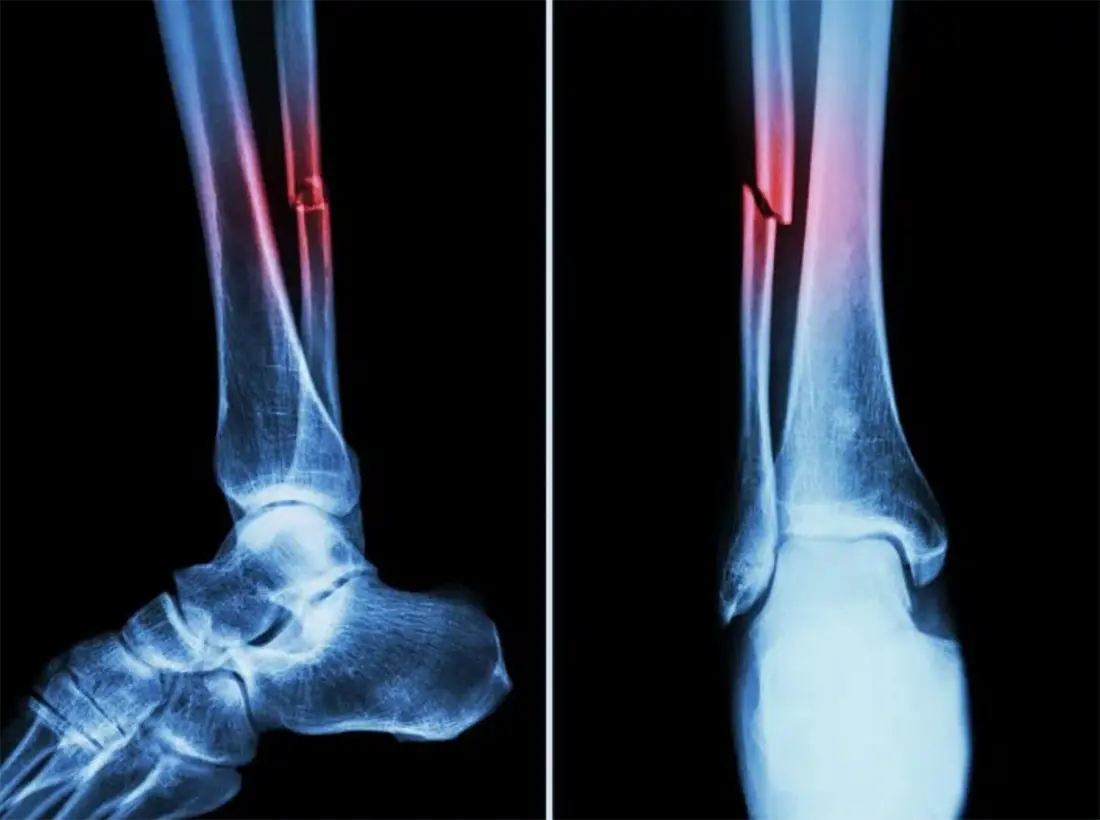

Fractures occur when the bones break due to a huge force exerted on them. Anyone can get them but young children and the elderly are especially vulnerable as their bones are brittle. It is also a common form of sports injury for athletes due to the high impact nature of their activity.

Whichever the case, fractures are a serious injury that requires immediate medical attention from an orthopaedic clinic. The doctors will reset them back to position or may perform surgery. After that, time must be taken for recovery as it is equally important as treating the bones. We will show what you should do in order to have a speedy recovery from your fracture.

Usually when your fracture has been assessed and reset, you may need to wear a cast to prevent unnecessary movement of the bones. This ensures that fracture is swiftly mended during the reparative stage. Depending on your injury, you could wear a removable cast or a plaster cast. Serious injuries would need to have metal fixings either internally on the bone or externally to keep the bones in place.